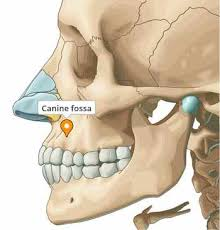

If it is lower down on the maxilla as the first two images suggest then it would be easier to check but just sticking your finger in your mouth and feeling if the bone above your teeth slants back slightly

If it is lower down on the maxilla as the first two images suggest then it would be easier to check but just sticking your finger in your mouth and feeling if the bone above your teeth slants back slightly